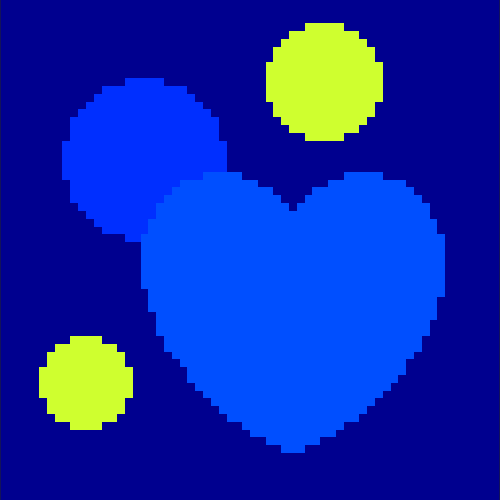

The first data set consists of a heart-shaped region and three circles on a static background (see figure 1 (a)). The two smaller circles are assumed to belong to

the same tissue type and therefore to the same subregion, which causes a total of four subregions, including the background. To simulate a more realistic application of dynamic SPECT

imaging, we used a synthesized representation of a rat liver as a second data set (see figure 1 (b)). The temporal concentration curves used to simulate the data sets

are shown in figure 2. As before, the total number of subregions was chosen to be equal to four in order to provide a both simple and realistic shape model.